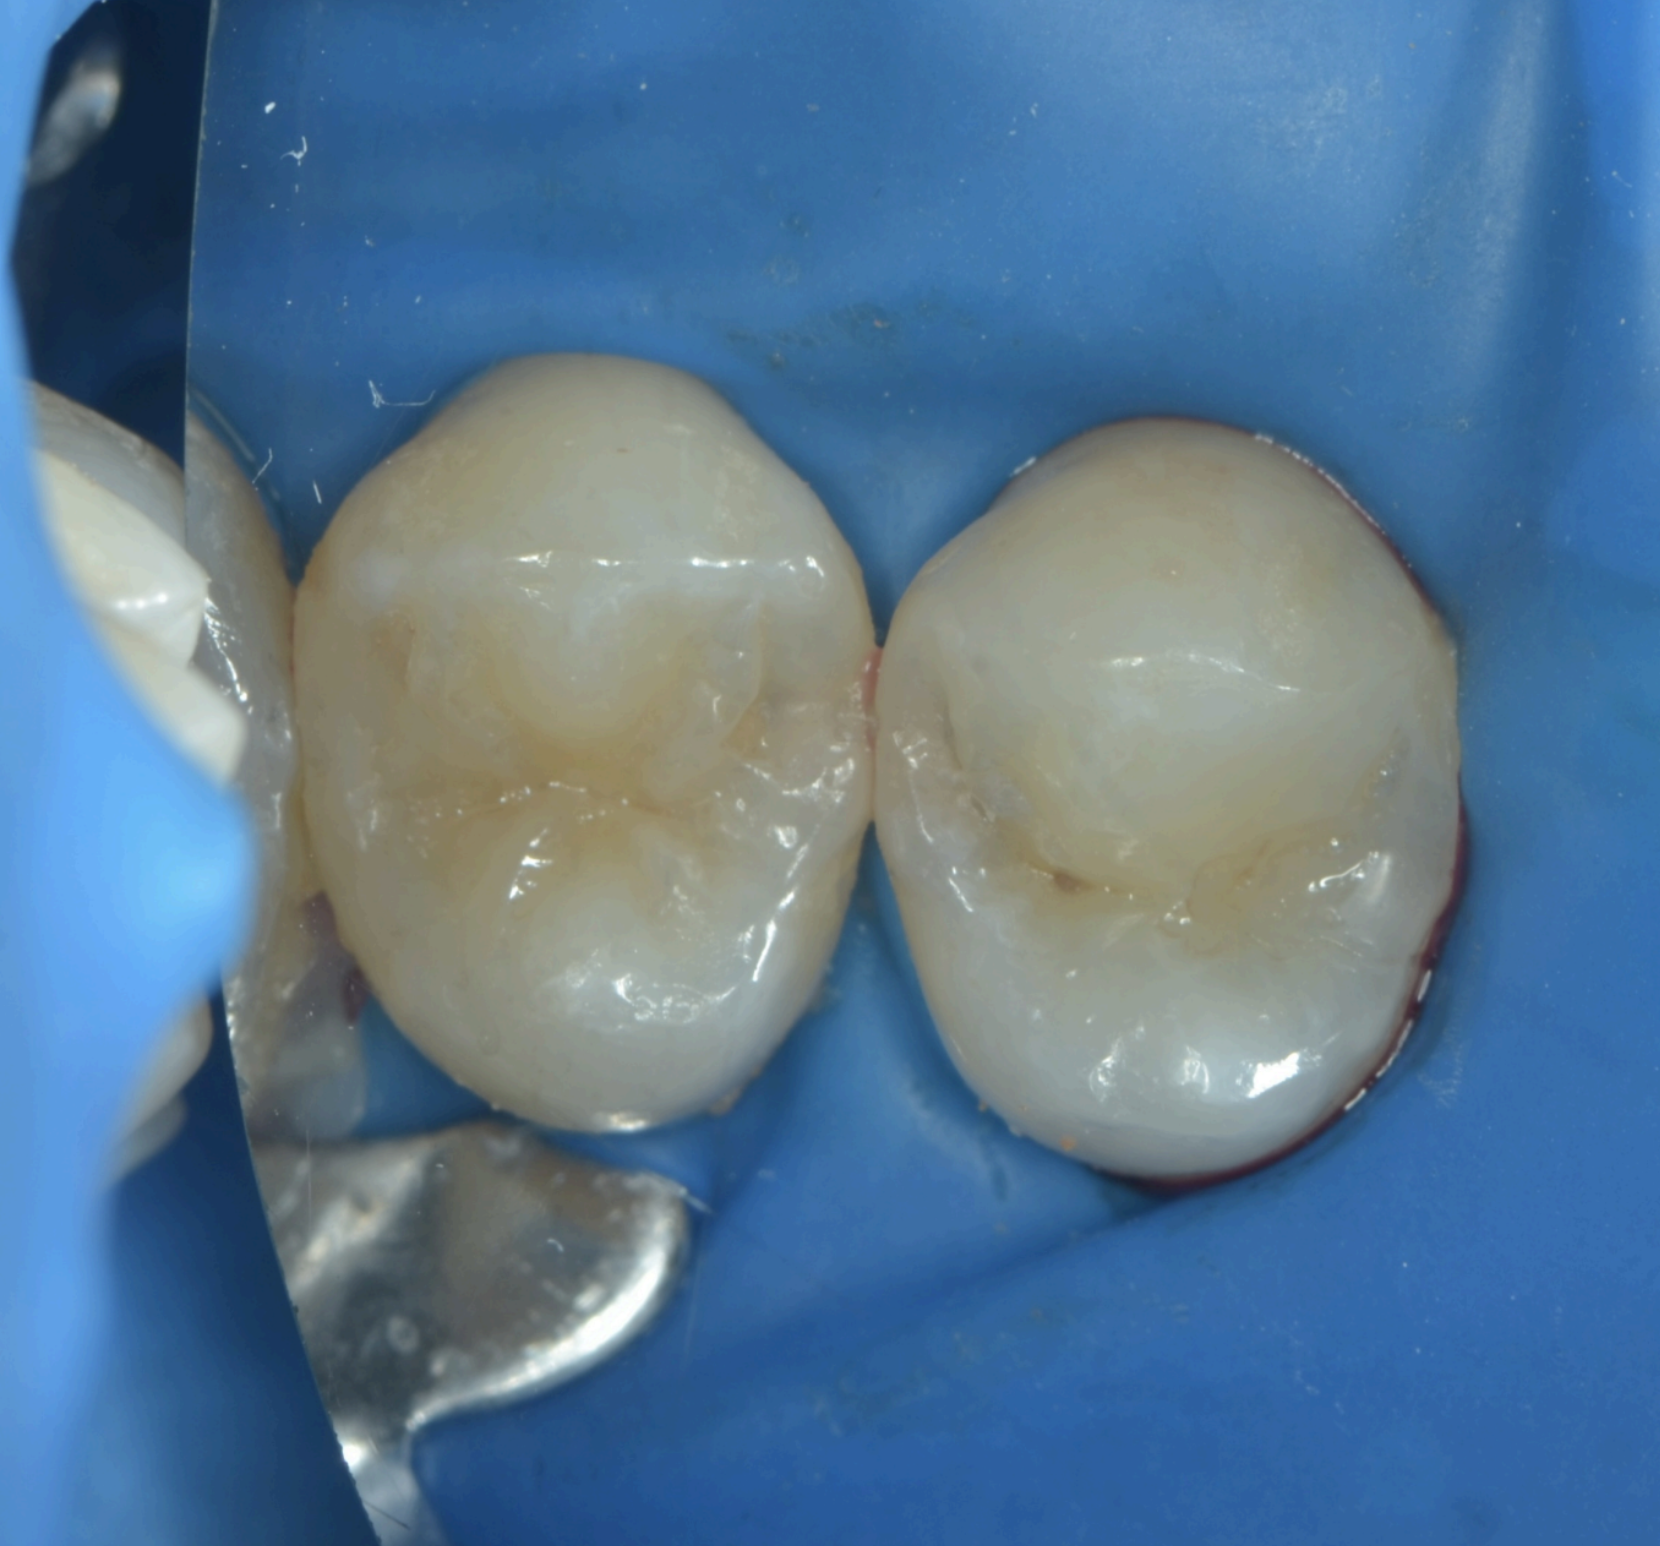

In cazul acestui pacient, acest tip de carie s-a format la nivelul premolarului 1 (dintele din dreapta). Deoarece bacteriile au inceput sa erodeze smaltul dentar la nivelul contactului cu dintele vecin, caria nu este mereu evidenta atunci cand privim dintele dinspre fata ocluzala (cea pe care se mesteca), ci ea se prezinta mai degraba ca o umbra cenusie, observata de catre medicul stomatolog prin uscarea cu aer a suprafetelor.

Tratamentul acestor carii implica curatarea mecanica a tesuturilor afectate de carie. Astfel, se indeparteaza automat unul din peretii de sustinere a dintelui. Daca ne imaginam un dinte ca fiind o cutie cu capac (capacul fiind suprafata pe care se mesteca), in aceasta procedura se va desfinta unul din peretii verticali, sau amandoi peretii, in functie de extinderea cariei.